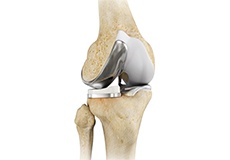

Total Knee Replacement

Total knee replacement, also called total knee arthroplasty, is a surgical procedure in which the worn out or damaged surfaces of the knee joint are removed and replaced with an artificial prosthesis.